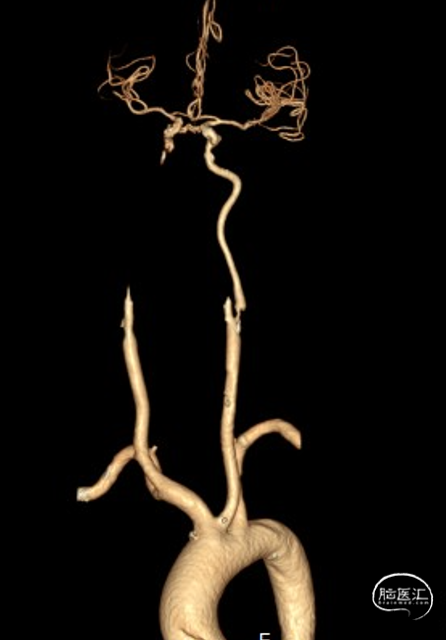

头颈部CTA

DSA